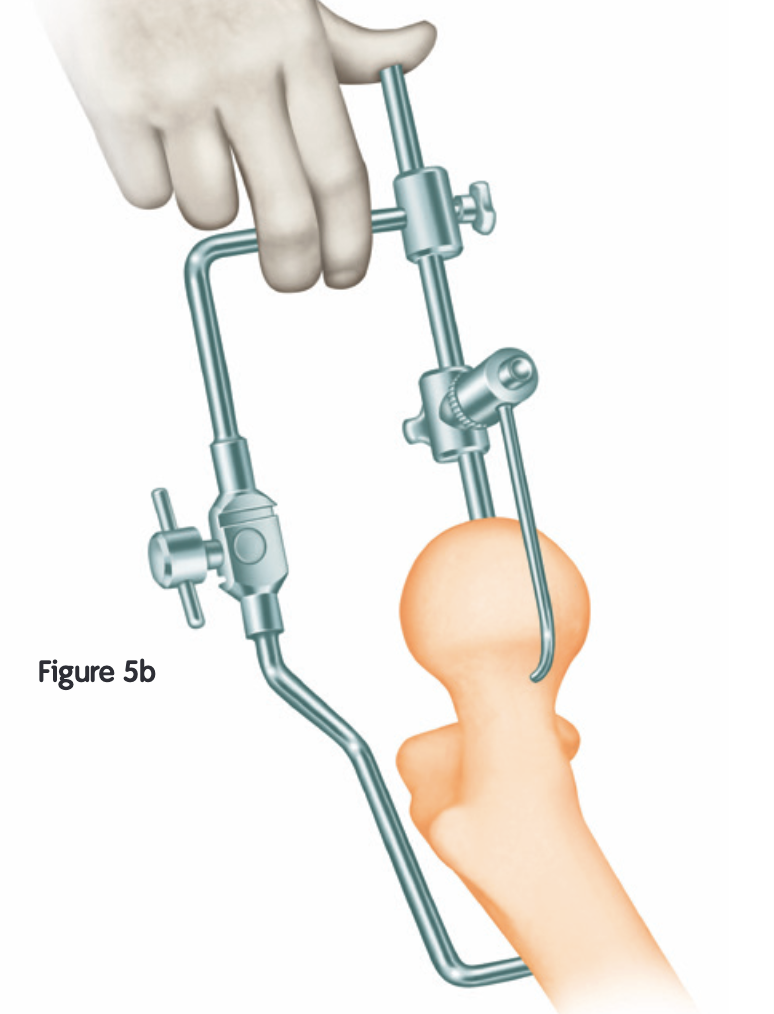

Technique

Techniques

Birmingham Resurfacing

Smith&Nephew Birmingham Resurfacing PDF

Avoid

- notching

- varus

- open acetabulum

Technical issues

Vumedi custom guides Birmingham resurfacing